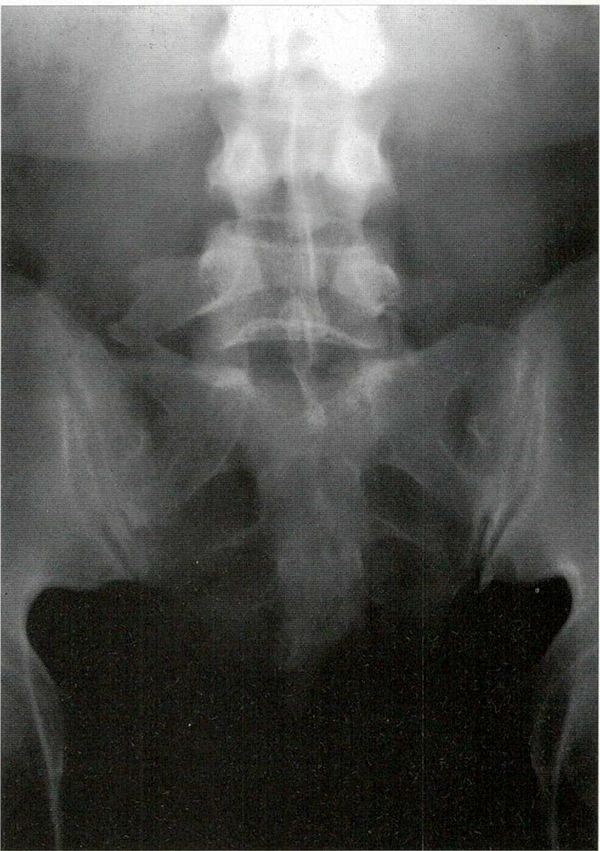

Caso 1: paciente de sexo femenino y 59 años de edad, con antecedentes de linfoma primario de piel, consultó por dolor radicular y paresia del miembro inferior izquierdo en el territorio L5. Las imágenes por resonancia magnética (IRM) de la columna lumbar mostraron a nivel foraminal y extraforaminal en L5-S1 un tejido blando hiperintenso con respecto al líquido cefalorraquídeo (LCR) que Infiltraba los tejidos vecinos y se introducía dentro del canal a través del foramen (Fig. 1). La paciente fue tratada con 16 mg/24 horas de dexametasona y antiinflamatorios no esteroideos 72 horas antes de ser llevada a cirugía para tomar biopsia y liberar la raíz nerviosa afectada.

Fig. 1. IRM axiales ponderadas en TI que muestran un tejido blando hiperintenso con respecto al LCR que ocupa las regiones foraminal y extraforaminal izquierdas